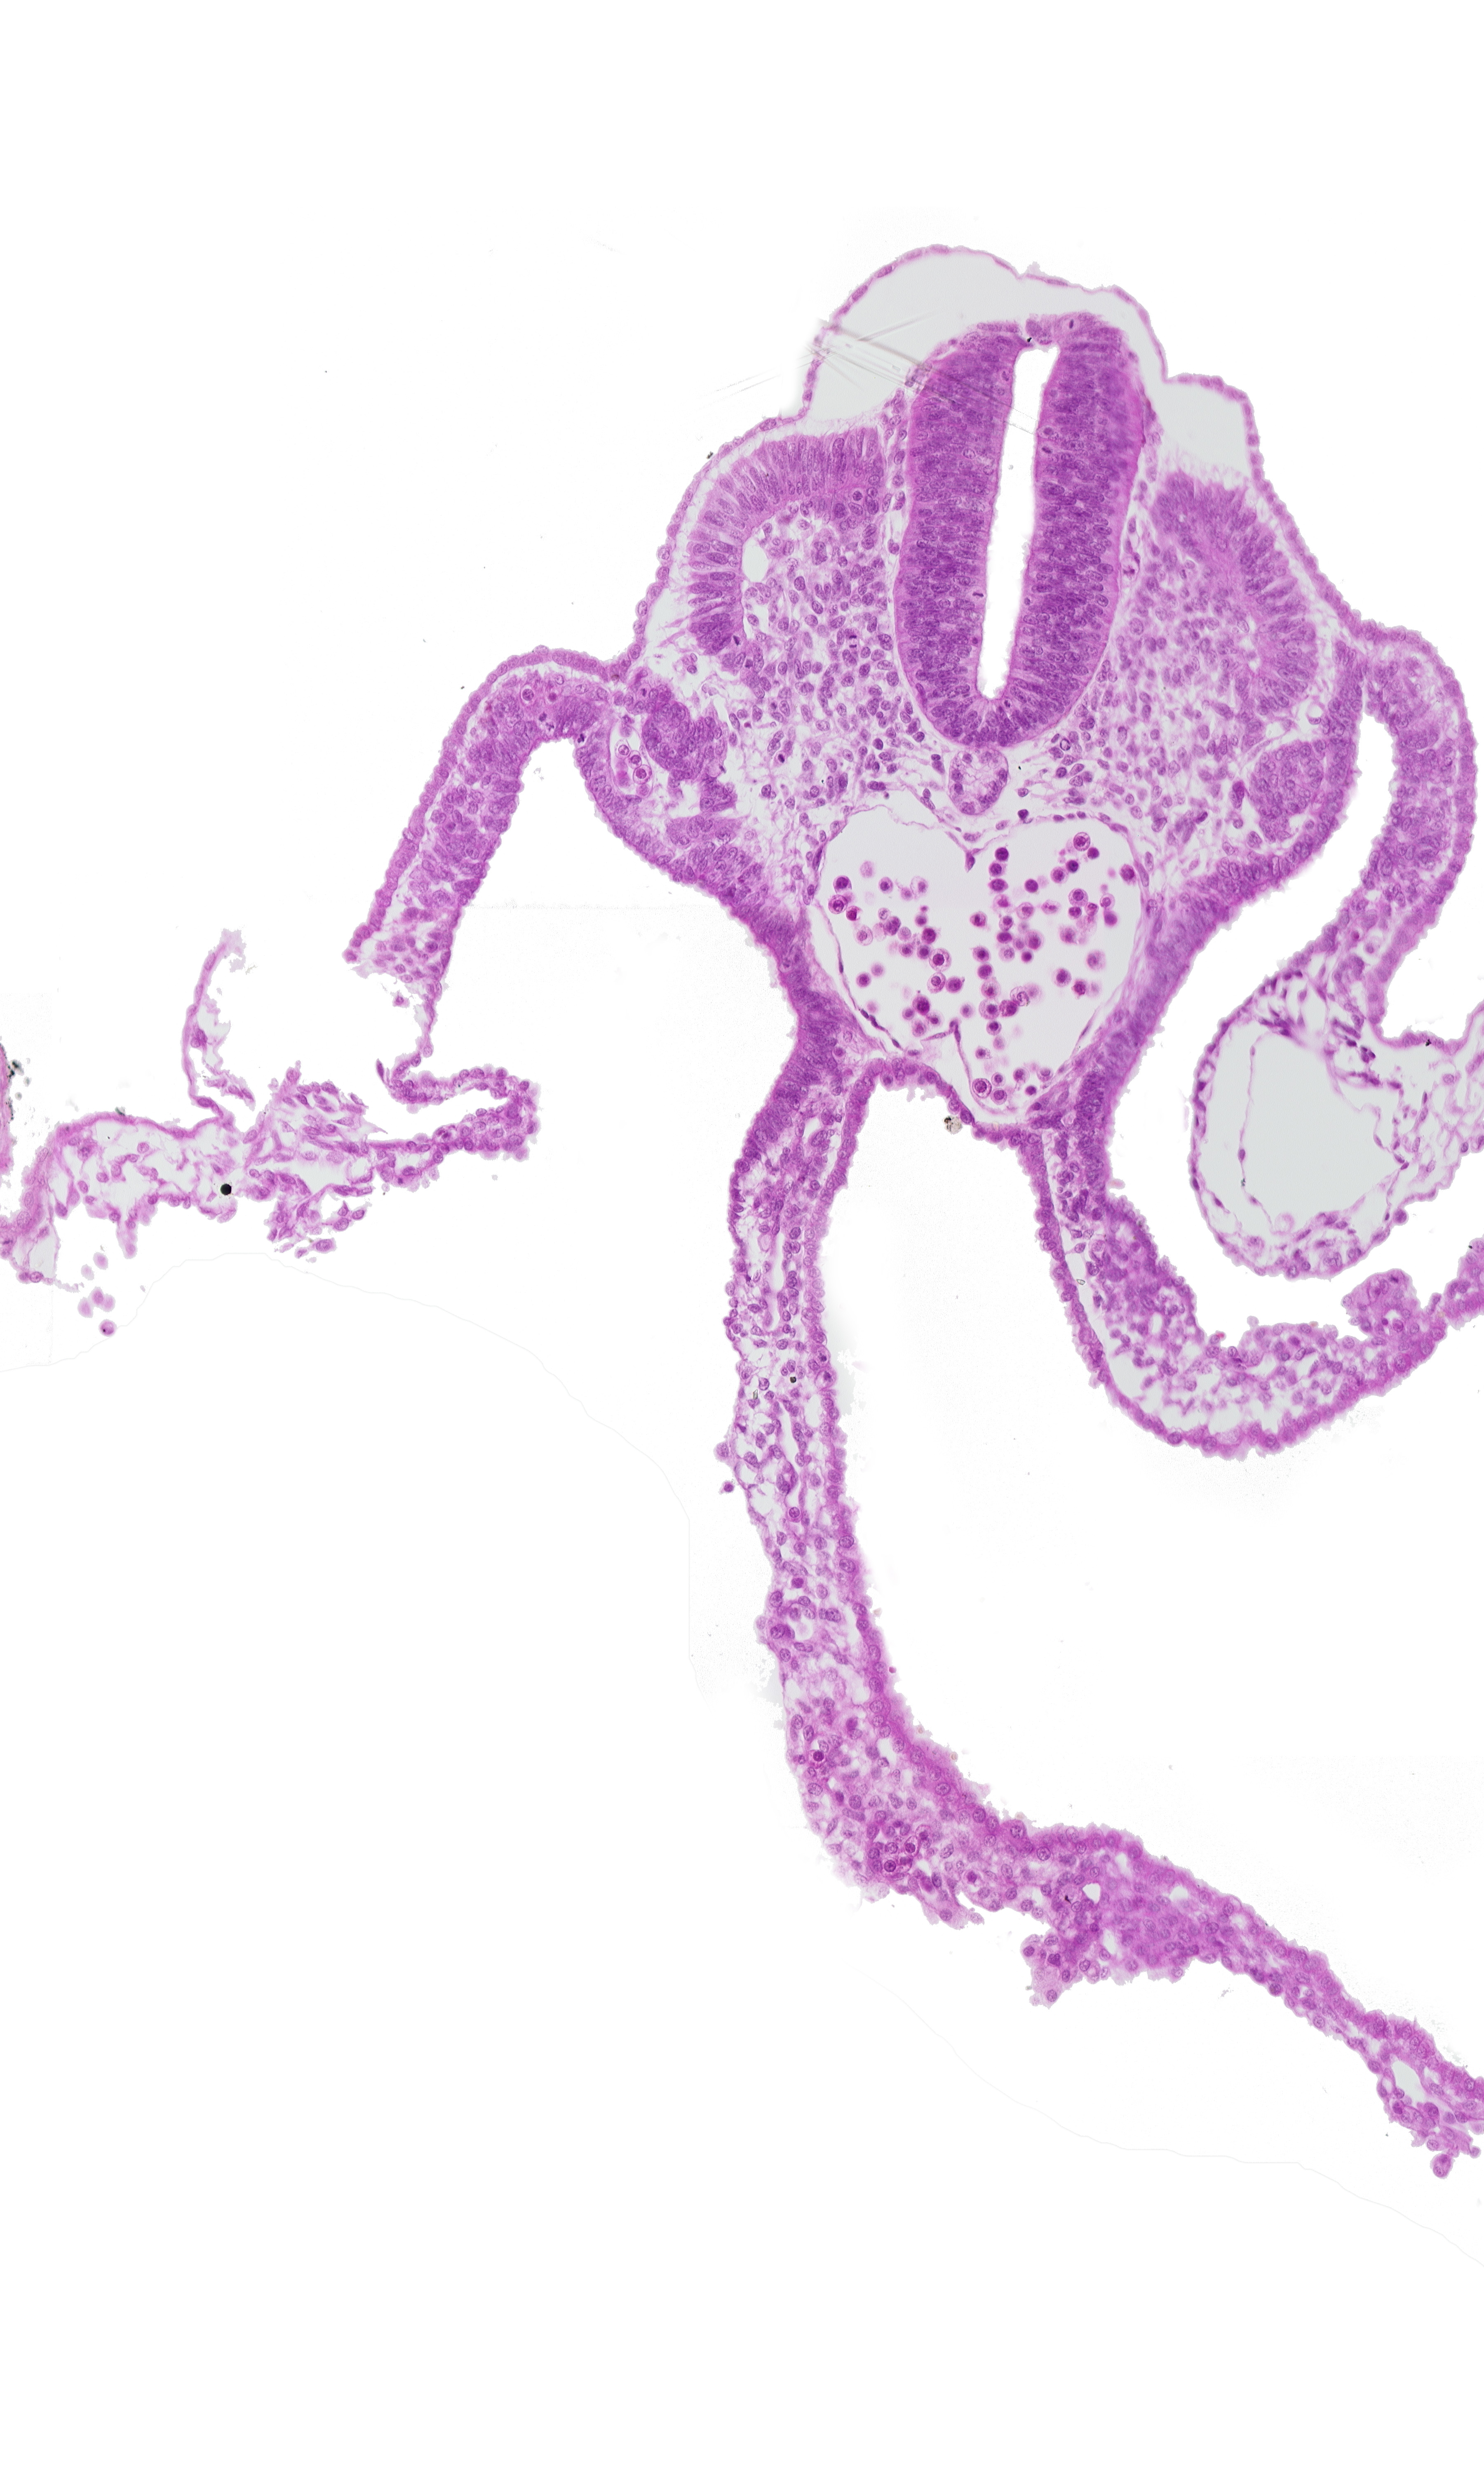

Carnegie Embryo #8943 | Location: 07-01-03

Keywords: amnion attachment, amniotic cavity, artifact separation(s), dermatomyotome 11 (C-7), left umbilical vein, mesonephric vesicle(s), midgut, peritoneal cavity

Source: The Virtual Human Embryo.